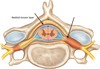

posterior funiculus

Name the structure.

lateral funiculus

Name the structure.

anterior funiculus

Name the structure.

anterior horn

Name the structure.

lateral horn

Name the structure.

posterior horn

Name the structure.

gray commissure

Name the structure.

central canal

Name the structure.

posterior root

Name the structure.

anterior root

Name the structure.

posterior root ganglion

Name the structure.

posterior median sulcus

Name the structure.

anterior median fissure

Name the structure.

epidural space

Name the structure.

subarachnoid space